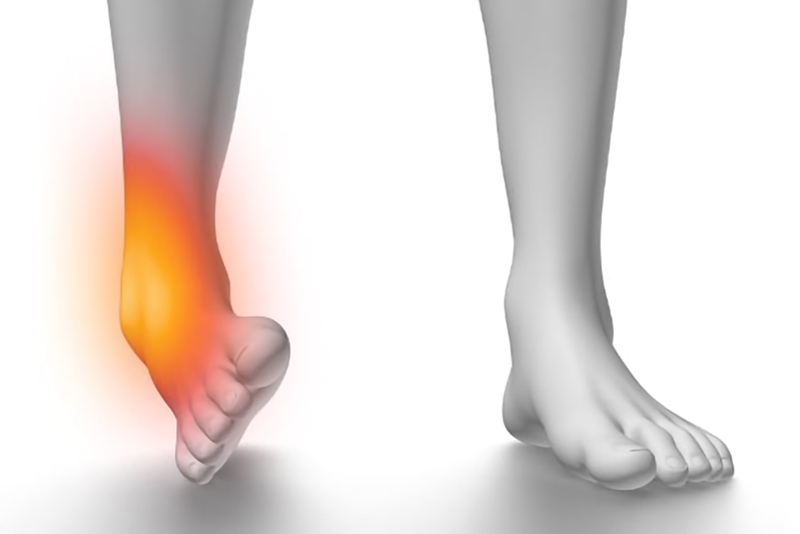

Les Entorses

Les entorses font partie des blessures articulaires les plus fréquentes, aussi bien chez les sportifs que dans la vie quotidienne. Elles peuvent toucher différentes articulations : cheville, genou, poignet, doigt…